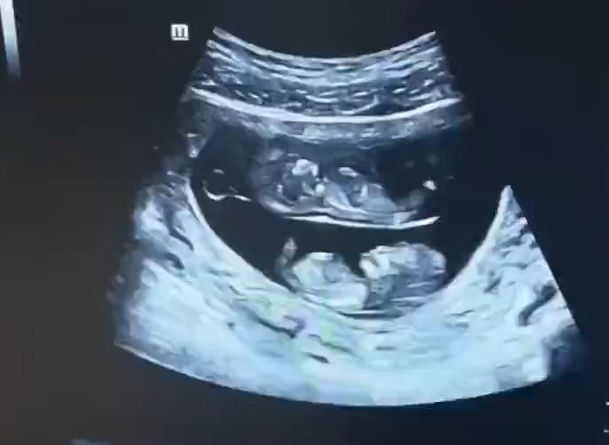

您的位置:跨度國際官網 > 母嬰